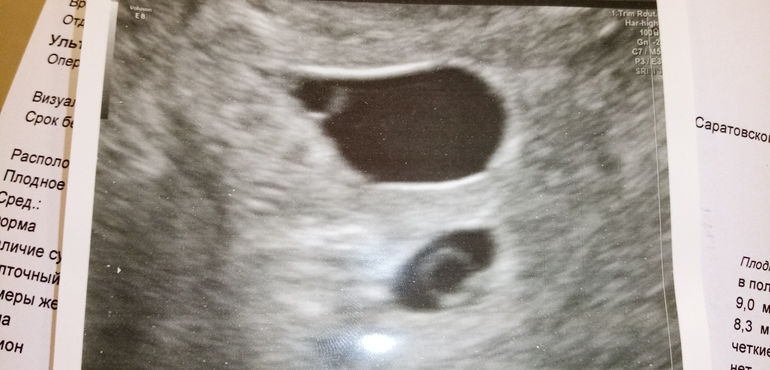

Огромное плодное яйцо!

5 нед 3 дня. Это нормально при двойне такая картина? (Сердцебиение есть у обоих) Я боюсь что в верхнем поделилась яйцеклетка на 2, или на таком сроке уже было бы видно всех жителей?

Почему вы считаете что огромное? В сравнении со вторым? Второе тоже может быть большое , только в другой плоскости надо смотреть.

По размерам что самое удивительное они одинаковы!!! Сердцебиение есть, даже цифры размеров одинаковы, а яйца так различаются, сегодня побегу в ЖК, УЗИст в принципе не врач, поэтому хочу для своего спокойствия проконсультироваться.